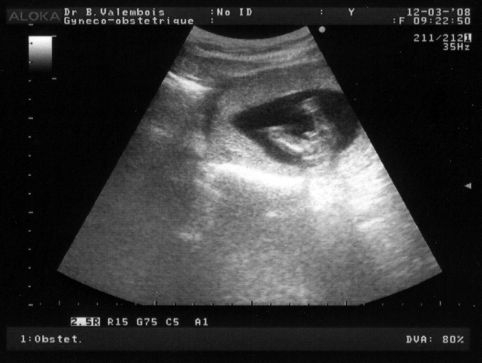

Dès que le gynéco a posé la sonde sur mon ventre, tu avais les jambes bien écartées et le zizi bien visible, aucun doute possible! Donc tu t'appelleras Elliott... C'est ça le bonheur!

Après, on a regardé ton profil, tu gigotes beaucoup mais le gynéco a réussi à prendre une superbe photo de toi...